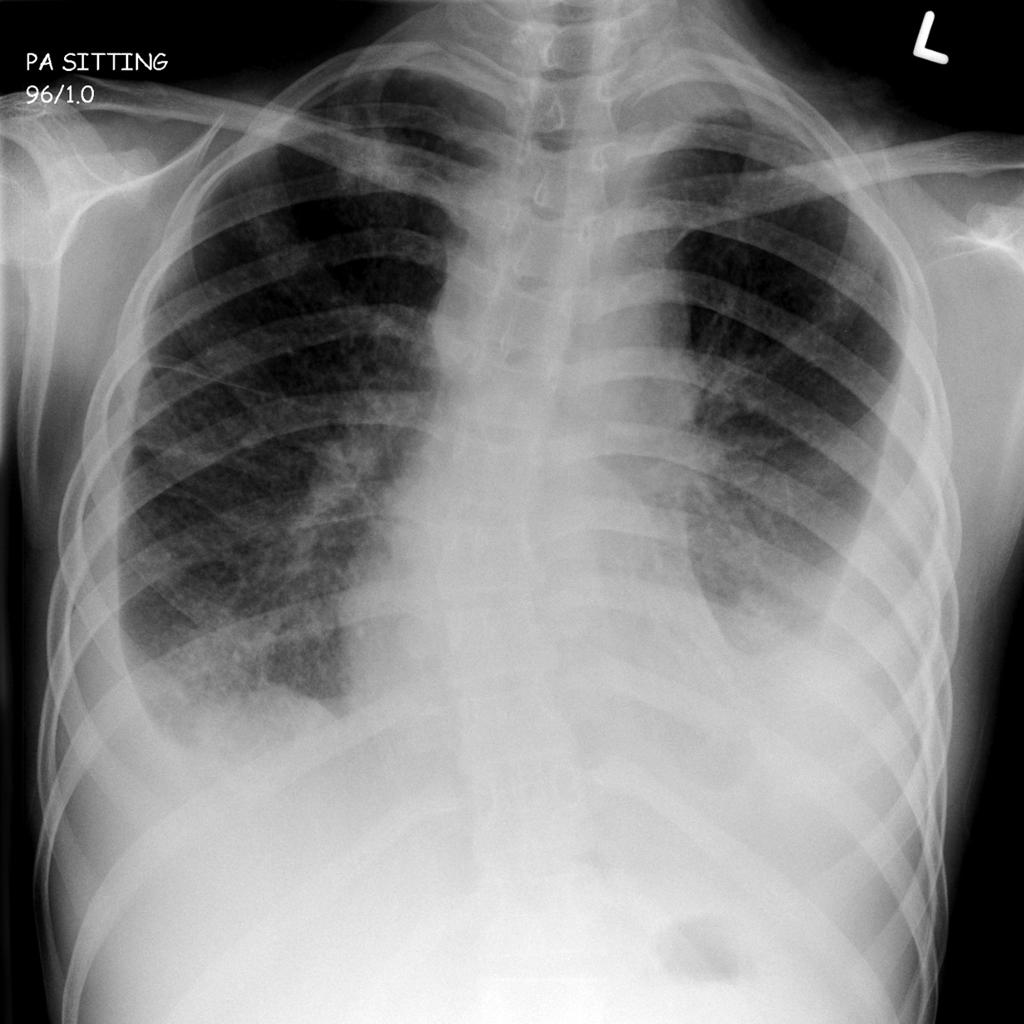

Диссеминированная форма

Эту форму туберкулеза можно поделить на острую, подострую и хроническую. Как правило, развивается остро со стремительным распространением туберкулезных палочек по всему организму.

Выделяют еще одну классификацию в зависимости от способа распространения микобактерий:

• гематогенное — на рентгене проявляется более крупным размеров очагов, находящихся в верхних отделах легких;

• лимфогенное — очаги среднего размера, размещенные преимущественно в нижних отделах;

• лимфобронхогенное — характерно одностороннее поражение в нижних отделах легкого.

То, как выглядит туберкулез на снимке, зависит как от характера его распространения, так и от остроты процесса. Наиболее характерный подтип диссеминированного туберкулеза — милиарный туберкулез. Он представляет собой острую, чаще всего гематогенную инфекцию.

Ниже перечислены основные его признаки на рентгене:

• большое количество мелких очагов, несколько миллиметров в диаметре;

• очаги равномерно распространены по всему легочному полю;

• иногда очаги сливаются;

• корни легких несколько приподняты;

• иногда объем легочной ткани становится меньше.